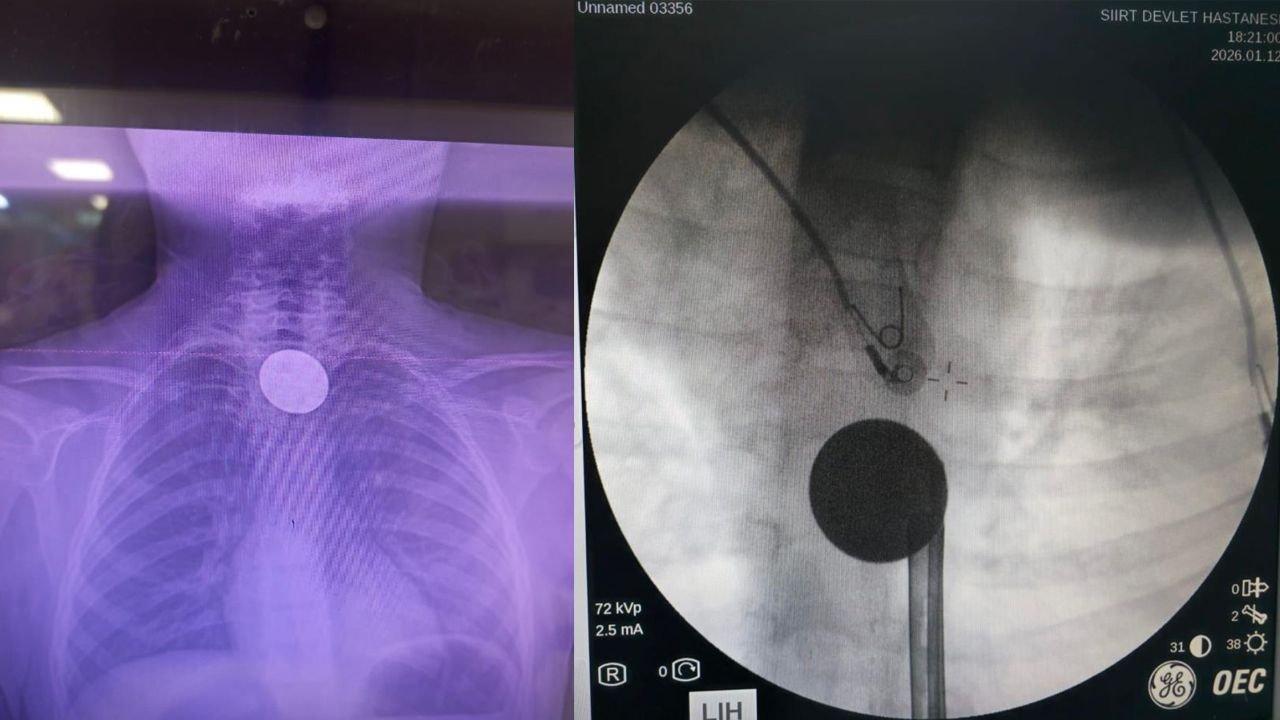

Yabancı cisim yutma şikayetiyle ailesi tarafından Siirt Eğitim ve Araştırma Hastanesine getirilen 8 yaşındaki Y.K., yapılan ilk değerlendirme ve görüntüleme tetkiklerinin ardından ilgili branşlarca operasyona alındı. Y.K.'nın yemek borusuna kadar ilerlediği tespit edilen madeni para, gastroenteroloji uzmanı Dr. Yaren Dirik ve kulak burun boğaz hekimi Yasin Gökçınar tarafından müdahale edilerek çıkartıldı. Operasyonun ardından bir süre gözlem altında tutulan Y.K., tedavisinin tamamlanmasıyla taburcu edildi.

Siirt Eğitim ve Araştırma Hastanesi Başhekim Yardımcısı Uzman Dr. Burak Özkan, çocuk hastalarda yabancı cisim yutma vakalarının ciddi riskler oluşturabileceğini söyledi. Uzm. Dr. Özkan, "Hastanemize başvuran 8 yaşındaki hastamızın yemek borusuna kaçan madeni para, gastroenteroloji ve KBB ekiplerimizin koordineli ve titiz çalışmasıyla herhangi bir komplikasyona yol açmadan başarılı bir şekilde çıkarılmıştır. Operasyon süreci sorunsuz geçmiş olup hastamızın genel durumu iyidir" dedi.